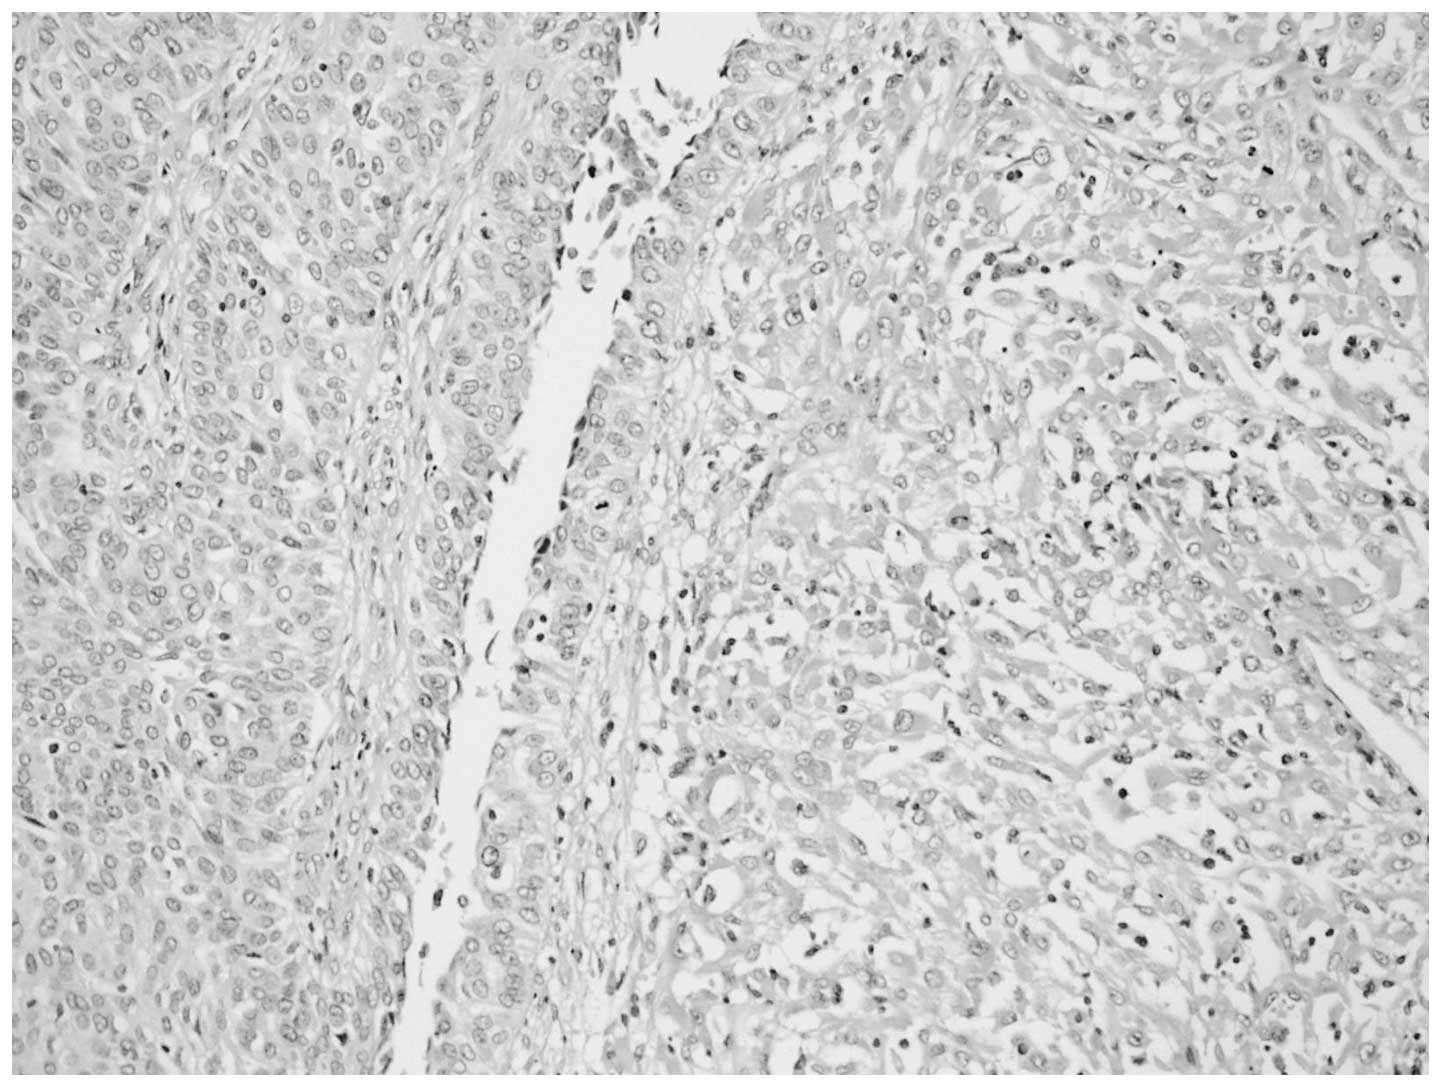

Macroscopic examination of the 13×8×6-cm nephrectomy specimen revealed a 8×5×4-cm tumoral mass in the renal pelvis. The cut section of the mass was gray-white in color, with a hard consistency. Areas of extensive necrosis were also present. The tumor had invaded the full-thickness of the renal pelvic wall and peripelvic adipose tissue. Furthermore, invasion into the renal parenchyma was observed. Histological examination of the tumor showed a malignant neoplasm comprising of epithelial and mesenchymal components, which were largely separated from each other (Fig. 2). However, in certain areas, the epithelial component blended into the sarcomatous component, generating a histological transition between the two. The sarcomatous areas primarily consisted of spindle cells, which were full of eosinophilic cytoplasm. Immunohistochemical staining was performed using a panel of markers, including cytokeratin, vimentin, Ki-67 antigen and p53. The epithelial portion of the tumor was found to stain positively for cytokeratin (Fig. 3) and the sarcomatoid spindle cells were observed to stain positively for vimentin, but negatively for cytokeratin (Fig. 4). The tumor cells in the epithelial and sarcomatous components were also found to express p53 protein in the nuclei. The expression level of p53 was >10%. Furthermore, the Ki-67 labeling indices were >20% in all of the tumor cells. Due to the advanced age of the patient, chemotherapy and radiotherapy were not administered. The patient was discharged six days after surgery and no recurrence was observed after eight months.

Figure 3

Immunohistochemical staining showing immunoreactivity for cytokeratin in the epithelioid cells of the carcinosarcoma. Magnification, ×20.

Due to the similar microscopic appearance of carcinosarcomas and sarcomatoid carcinomas, immunohistochemistry may be a useful diagnostic adjunct for differentiating between these tumors. In the present case, antigenic determinants that were specific for epithelial cells, such as cytokeratin, were identified. Furthermore, the sarcomatous component was characterized by strong staining for vimentin. In addition, the lack of expression of keratin markers in the mesenchymal component further confirmed the diagnosis of carcinosarcoma.